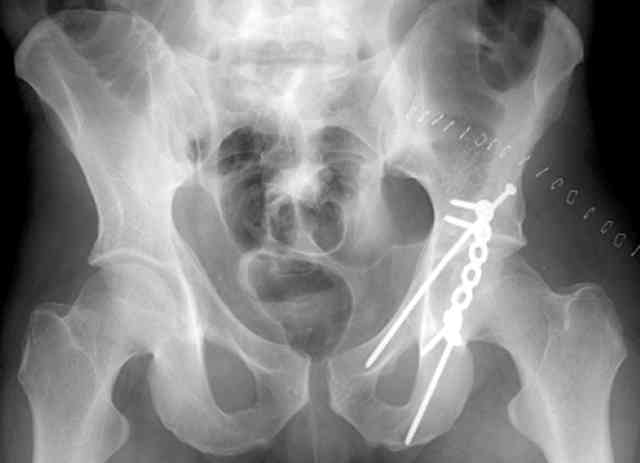

Routine Fixation

• AC Screw

• PC Neutr Plate

• Others

• The unstable caudal segment is secured by the lower 2 plate screws and the AC medullary screw... always assure that your fixation is sufficient to defeat the instability... part of your prop plan... but assure it before you close... it¹s your last chance... you shouldn't have to be pushing on the hip in contorted ways to determine your fixation stability...you can if that makes you 'comfortable'.

A CT scan will rarely lie to you...reveals your reduction and implants...we use it to assess, teach, grade, and try to get better next time.